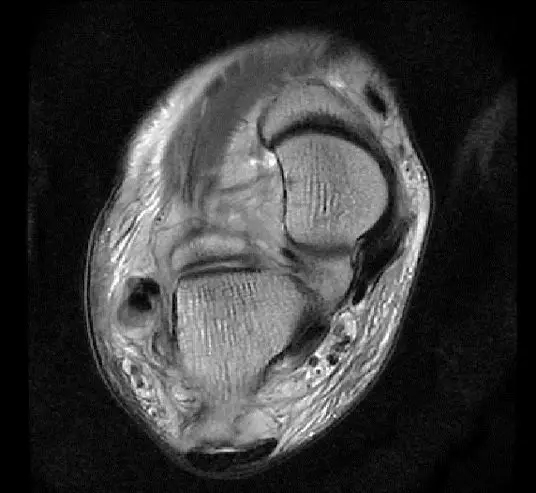

此片可以看到距腓前韧带和跟绯韧带有高信号大片的渗出病变,韧带结构松弛,增粗,这个地方可以看到腓骨前韧带的segond骨折块,所以考虑是踝关节外侧副韧带损伤,腓骨腱的segond骨折。